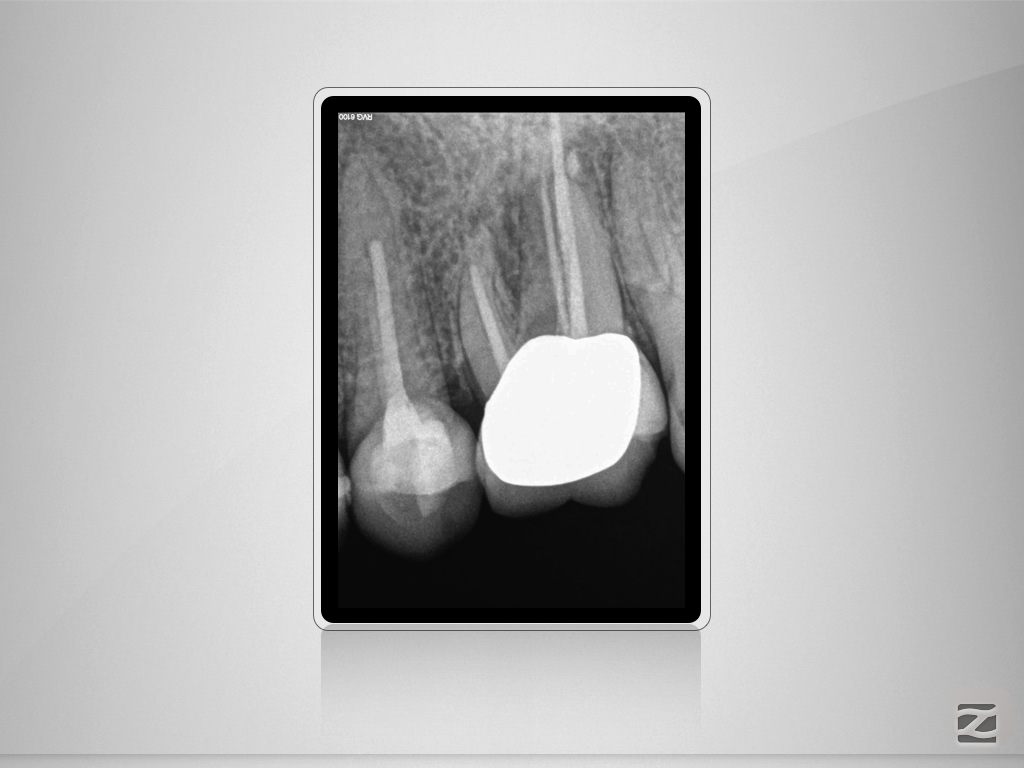

2526d-002

Enter Sandman